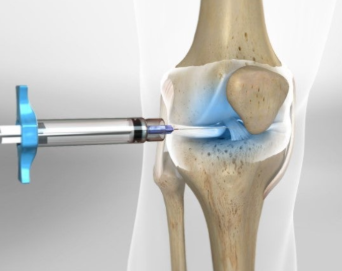

주사 치료: 초기에는 연골 주사(히알루론산 등)도 사용 가능. 연골손상이 크지 않을 때는 줄기세포, 자기골수 주사

주사 치료: 히알루론산 주사, 스테로이드 주사 등 사용.

⚑ 줄기세포 시술

정의: 줄기세포(주로 성체줄기세포, 예: 골수·제대혈 유래)를 채취해 최소한의 조작만 한 뒤, 주사 등의 방법으로 환자에게 다시 투여하는 시술

방법: 시술자는 주로 주사 혹은 시술(비수술) 방식으로 실시하며, 마취나 관절 절개 없이 진행. 자신의 골수에서 줄기세포를 추출해 정제 후 관절에 직접 주사하는 방식

범위와 효과: 비교적 작은 연골 결손, 초기 퇴행성 관절염에 이용되며, 통증이 적고, 시술 후 바로 일상 복귀가 가능. 줄기세포의 증식 능력이 무릎 연골 재생에 도움을 줄 수 있습니다